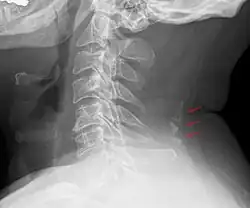

Bone tissue in the nuchal ligament.

Neck